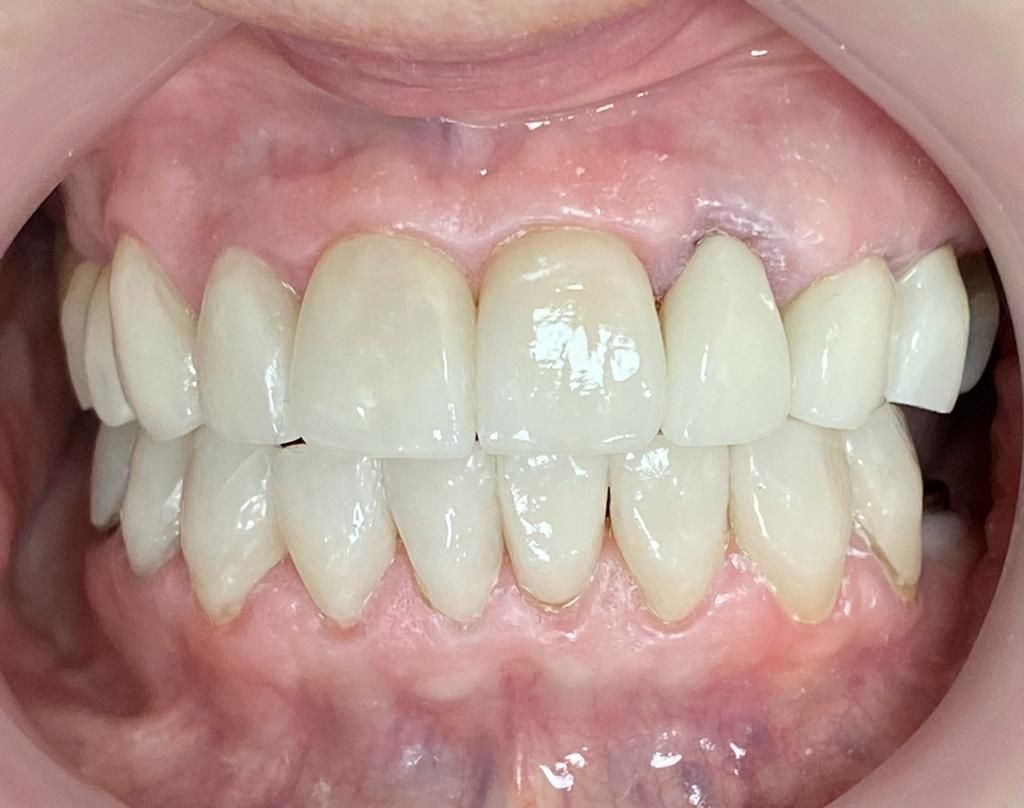

Contamos con odontología digital de vanguardia que nos permite realizar diseños de sonrisa personalizados, tratamientos de alineación dental mediante alineadores como alternativa a la ortodoncia convencional, así como la colocación de coronas y carillas de porcelana, fundamentales para lograr una sonrisa estética, armónica y funcional.

Diseño de sonrisa

Una alternativa inovadora para cambiar la forma y color de dientes es mediante el sistema U Venner de carillas de porcelana o de ceromero. Previamente se requiere de fotografías intraorales, toma de moldes dentales y toma de color dental. Excelente opción para diseñar una nueva sonrisa.